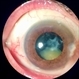

- subluxation of lens, lens luxation, Luxated lens to anterior segment

- Patient 61 years old, Female, subta low vision after blunt trauma. In the anterior segment photograph, the presence of a lens in the anterior chamber is observed. In the previous follow-up OCT, the disorganization of this follow-up is clear. Above all, the documentation of these cases is essential for future decisions. This patient was urgently referred for a surgical procedure, mainly to control the intraocular pressure, which was at 60 IOP.